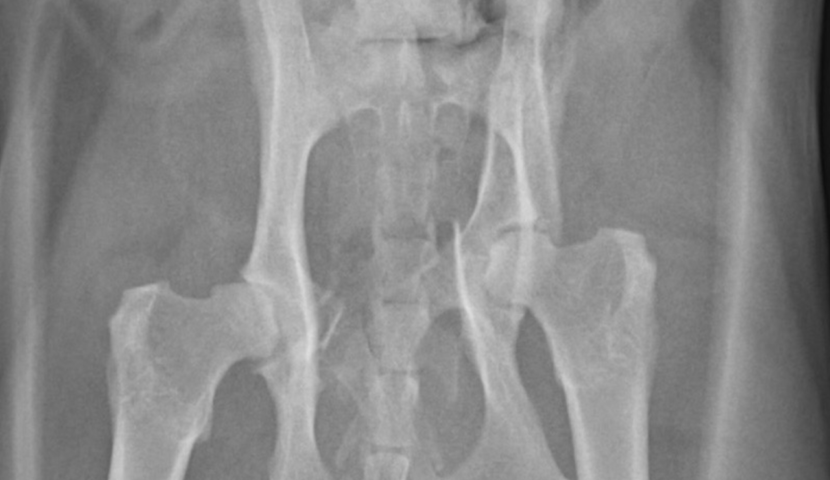

| この猫ちゃんは手術して5ヶ月を経過しておりますが、歩行、排便に問題がなく、良好な経過を辿っております。 早期に手術を行うことで、骨折に伴う疼痛の改善、将来的な骨盤狭窄の予防ができます。 当院では整形外科外来をわらび院で行っており、高度な整形外科の設備(各種インプラント、Cアームなど)を整えております。 このような症状があれば是非一度ご相談ください。 |